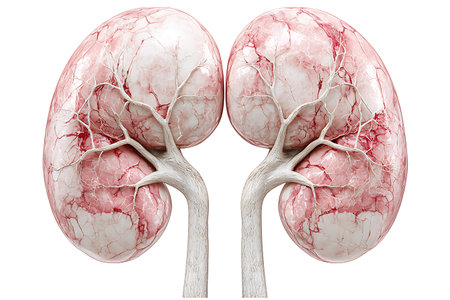

3 d illustration of human kidneys anatomy (human organs)

Human Kidneys Anatomical Model isolated on white background

Human Kidneys Anatomical Model isolated on white background

3d rendered illustration of kidneys

medical 3d illustration of the kidneys

3d rendered medically accurate illustration of a womans kidneys

Human kidney anatomy isolated on white background. 3D illustration. 3D rendering.

3d rendered medically accurate illustration of a womans kidneys